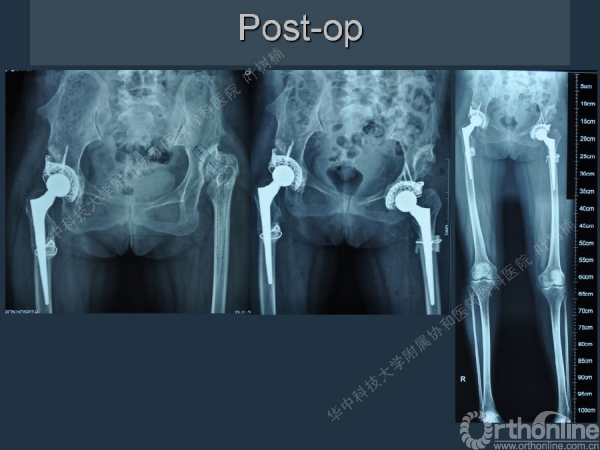

股骨侧翻修